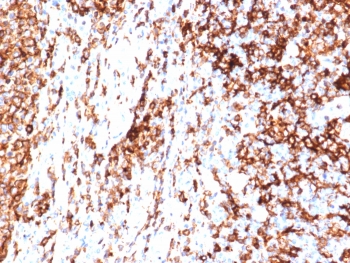

This mAb reacts with the beta-chain of HLA-DR antigen, a member of MHC class II molecules. It does not cross react with HLA-DP and HLA-DQ. The L243 antibody recognizes a different epitope than the HLA-DRA/6840R monoclonal antibody, and these antibodies do not cross-block binding to each other's respective epitopes. HLA-DR is a heterodimeric cell surface glycoprotein comprised of a 36kDa alpha (heavy) chain and a 28kDa beta (light) chain. It is expressed on B-cells, activated T-cells, monocytes/macrophages, dendritic cells and other non-professional APCs. In conjunction with the CD3/TCR complex and CD4 molecules, HLA-DR is critical for efficient peptide presentation to CD4+ T cells. It is an excellent histiocytic marker in paraffin sections producing intense staining. True histiocytic neoplasms are similarly positive. HLA-DR antigens also occur on a variety of epithelial cells and their corresponding neoplastic counterparts.